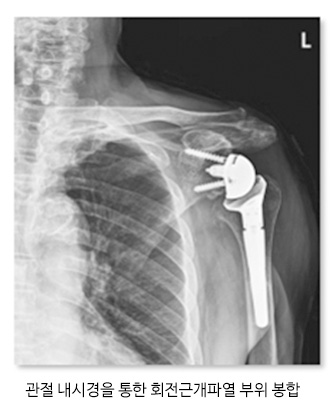

● 진단 회전근개 파열은 진단하기 위해서는 MRI를 촬영하여 어깨의 상태를 파악합니다. 가장 정확하게 확인하는방법은 관절조영술로 직접 보고 확인하는 방법이 있습니다. ● 치료 회전근개 파열은 조기에 진단을 하여 치료하는게 중요합니다. 힘줄이 완전히 끊어지지 않았다면 약물치료, 물리치료, 체외충격파치료 등 활용하여 치료를 시행하고 힘줄이 완전히 끊어 졌다면 관절 내시경 장비를 통하여 회전근개를 봉합하는 수술을 진행하고 끊어진 상태로 오래 방치했거나 피열 정도가 심해 봉합이 어려운 경우 인공관절 수술을 하기도 합니다. 관절내시경 ![]() ![]() |